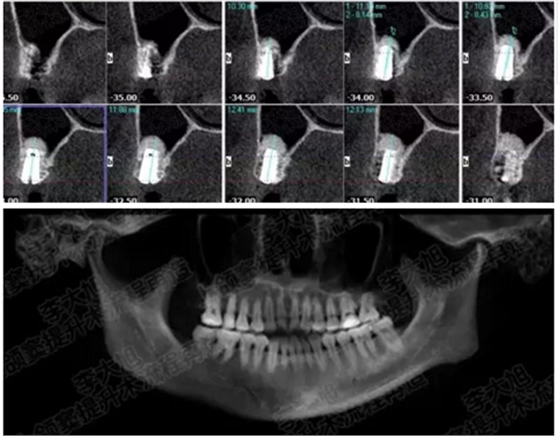

病例一

上頜竇多分隔3mm

05.png

提升8mm

06.png

07.png

修復(fù)時(shí)根尖片

08.png

09.png